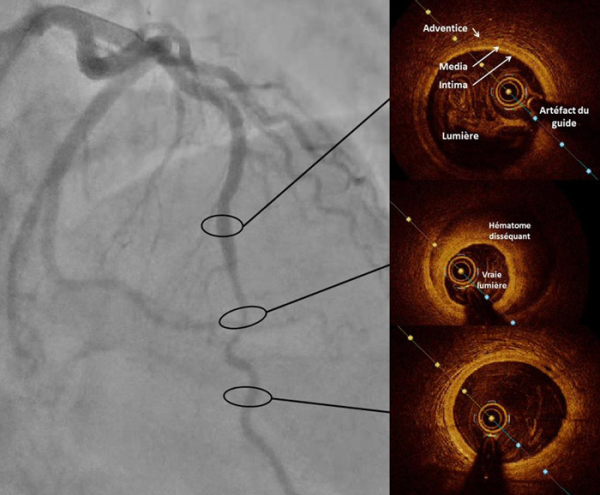

Figure 4A : Séquence d’imagerie endocoronaire par OCT

Figure 4B : Vidéo de séquence d’imagerie endocoronaire par OCT

L’imagerie endocoronaire n’est pas obligatoire pour le diagnostic de dissection coronaire spontanée. Elle peut s’avérer utile lorsqu’un doute diagnostic persiste, ou pour guider le traitement interventionnel. Très souvent, l’OCT (Optical Coherence Tomography) est préférée à l’IVUS (Intravascular Ultrasound) pour sa haute résolution spatiale (résolution axiale de 15mm). Le choix de notre équipe a été de réaliser une imagerie endocoronaire par OCT en phase aiguë.

Sur cet OCT, on peut visualiser l’hématome disséquant avec aspect en croissant de la fausse lumière. Ici, la fausse lumière, composée d’hématome intramural, enveloppe et comprime la vraie lumière. Il n’y a pas de porte d’entrée retrouvée sur cet examen. À noter qu’en amont et en aval de cette zone, on retrouve une artère sans plaque athéromateuse avec ses trois tuniques bien individualisables (intima, media et adventice).